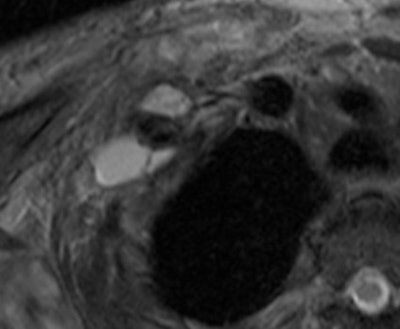

Young man who underwent a brachial plexus MRI examination following a motorcycle accident. A complex brachial plexus lesion is depicted. This case has been considered a true positive. All images courtesy of Dr. Alberto Tagliafico.

Patients ranged in age from 18 to 84 years. Their lesions detected by MRI represented a mix, including 35 root avulsions and brachial plexus cord injuries, 22 primary or secondary tumors, and four each entrapment syndromes, fibrous scars, and Parsonage-Turner syndrome.